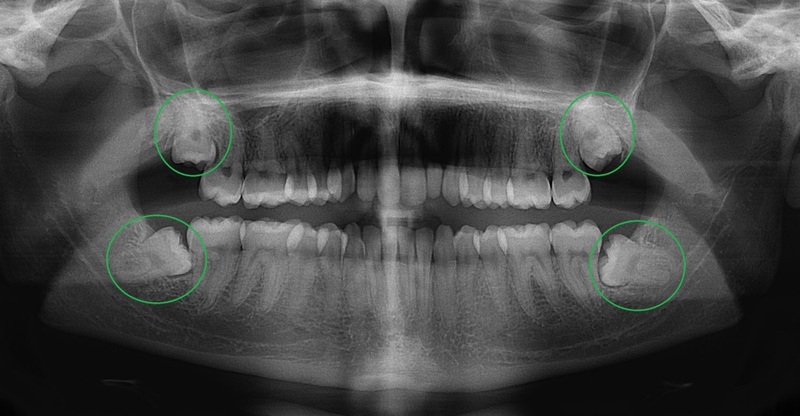

Chụp X-Quang

Dựa vào kết quả chụp X quang để kiểm tra hướng mọc. Xương xung quanh chân răng. Phân tích tình trạng và mức độ răng cần nhổ và đưa ra phương pháp thực hiện chính xác.